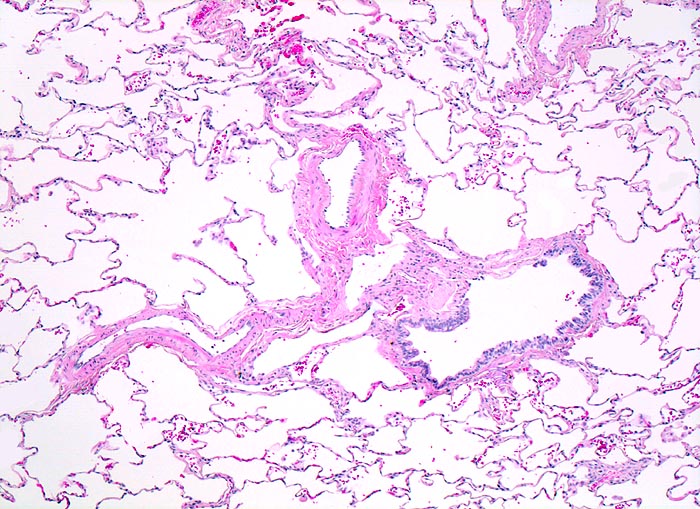

• In den sternförmigen Ausläufern finden sich erweiterte Endothelausgekleidete Lymphgefässe in der Nachbarschaft von Blutgefässen.

• Die erweiterten Lymphgefässe enthalten solide Tumorzellaggregate.

• Peritumorales Lungenemphysem (Traktionsemphysem).